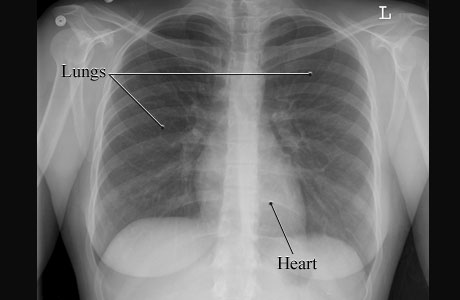

X-Ray of a Normal Chest